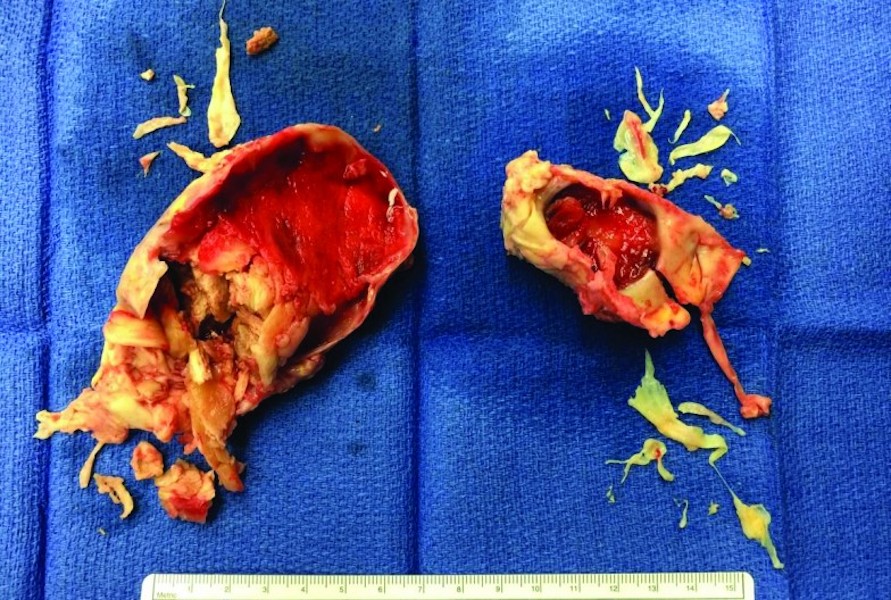

Extensive chronic clot removed from both of Kevin's lungs

Extensive chronic clot removed from both lungs.

• Kevin underwent successful PTE surgery with extensive chronic clots removed from both lungs on a Monday and was discharged on a Saturday.